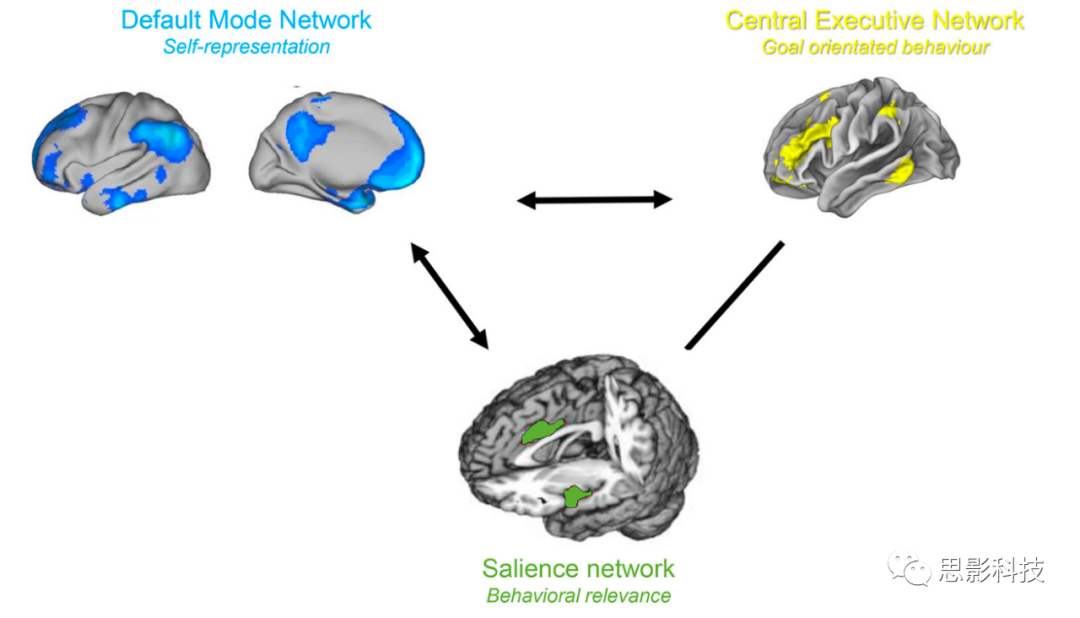

三重网络模型提供了一个通用的统一框架,可用于理解各种神经精神疾病。它认为,大脑疾病是由三个主要大脑网络内部和之间的异常相互作用引起的:自我表征的默认模式网络、行为相关性编码的突显网络,以及目标导向的中央执行网络。

疼痛刺激通常会导致负面的认知、情感和自主反应,表现为由中央通路处理的与疼痛相关的痛苦。这在解剖学上与编码疼痛刺激的行为相关性和中央交感控制网络的突显网络重叠。当疼痛持续的时间超过愈合时间并变成慢性时,与疼痛相关的体感皮层活动可能会与自我表征的默认模式网络功能性地连接,即,它成为自我感知的固有部分。这很可能是为了节省能量而进行的进化适应,通过将疼痛与消耗交感能量的行动分开。通过与前额顶叶中央执行网络的相互作用,这最终可能导致功能障碍。

三重网络模型是一种基于网络科学的方法,用于研究认知和情感障碍(30)。它声称,神经精神疾病是由三个关键大脑网络内部和之间的异常互动引起的。这三个网络包括自我表示的默认模式网络(31, 32),它最初由Raichle在2001年描述(33);行为相关性编码的突显网络(34)和目标导向的前额顶叶中央执行网络(34, 35),两者均由Seeley在2007年确定(34)(图4)。通常,中央执行网络和突显网络显示相关活动,而这两个网络与默认模式网络呈反相关(36)。突显网络作为默认模式网络和中央执行网络之间的开关(37-39)。这与这三个网络的提议功能是一致的。当突显网络识别到一个外部行为相关的事件时,它会减少以自我为中心、思绪漫游的默认模式网络的活动,并激活外部目标导向的中央执行网络来处理外部显著刺激。这三个关键网络内部和之间的功能连接在许多大脑障碍中都是异常的,包括抑郁症、焦虑症、精神分裂症和创伤后应激障碍(30)。我们提议,在慢性疼痛中,已知的三个疼痛通路可以扩展到三重网络模型,这将解释疼痛的慢性化以及常见的认知功能障碍。

图 4. 三重网络模型。突显网络和中央执行网络是相关的,而两者与默认模式网络呈反相关。

这一图表进一步阐明了三重网络模型中各个网络之间的相互关系和活动模式,特别是突显网络和中央执行网络的相关性,以及它们与默认模式网络的反相关性。这为理解这些网络在慢性疼痛和其他神经精神疾病中的作用提供了有用的框架。